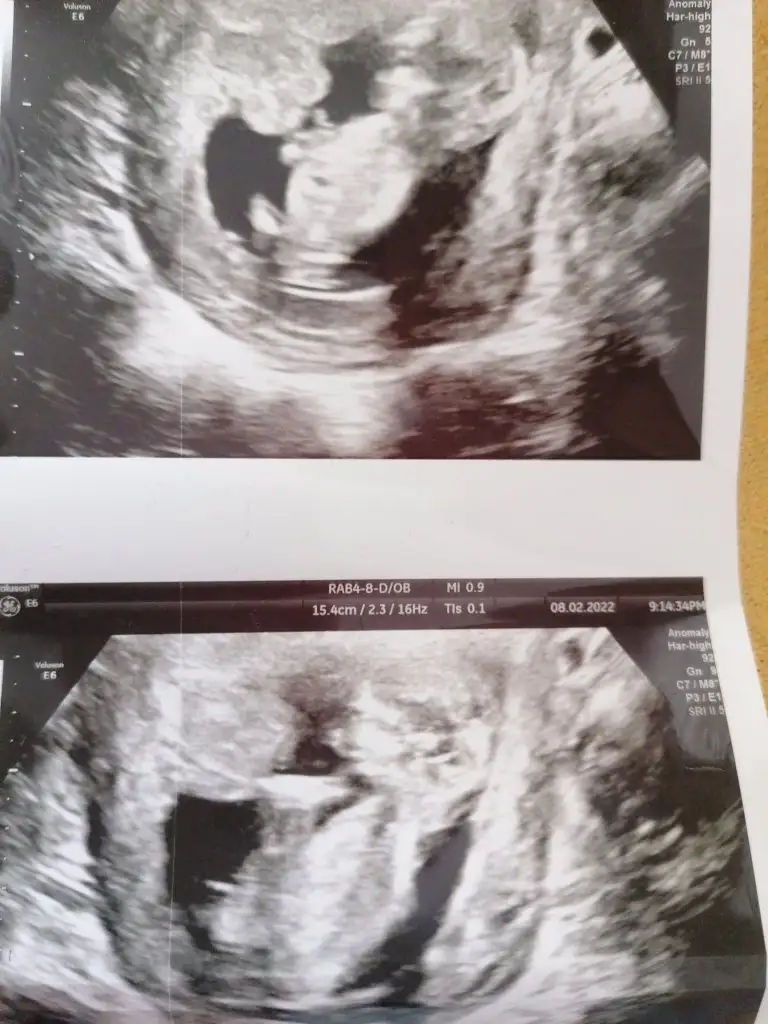

Net olmayınca bakmıyorum nubu karışık emin olamadım kız gibi sanki emin değilimIkra meyra banada tahmin yapabilir misin canım?? 12 haftalık

Kiz gibi sanki çok net değil USGBeni de yine atladınız sanırım...Ikra meyra